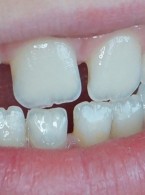

Pokrycie mnogich recesji dziąsłowych

metodą płata przesuniętego dokoronowo z wykorzystaniem przeszczepu podnabłonkowej tkanki łącznej i kolagenowego materiału ksenogennego po wcześniejszej rekonstrukcji połączenia szkliwno-cementowego - opis przypadku